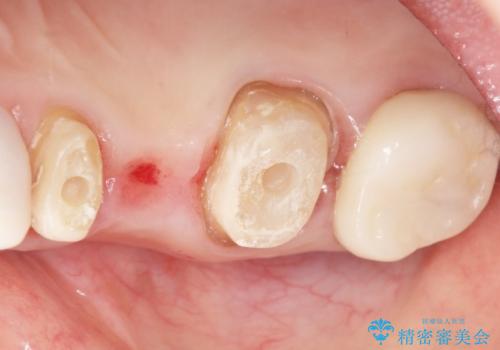

- 被せ物と歯ぐきの境目が黒いことを気にされ、来院された患者様です。

精査したところ、メタルボンドクラウンの金属部分が露出し黒く見えていました。

患者様のご希望により、金属を使わないオールセラミックのブリッジによる補綴治療を行いました。

金属の土台も除去し、ファイバーコア(金属を使わない強度のあるしなやかな土台)へやりかえました。